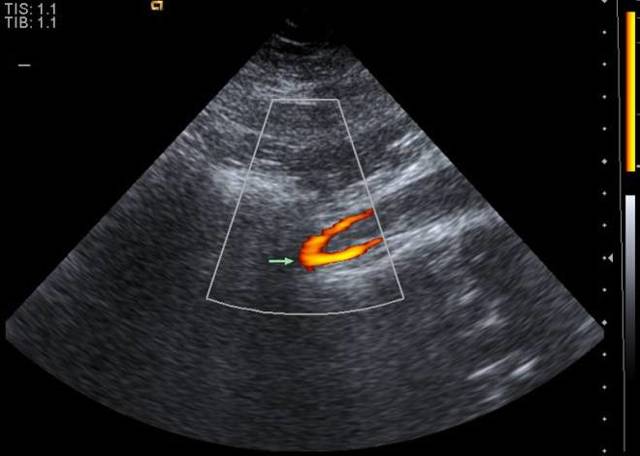

Проводится с импульсным допплером, что делает возможным получение цветного 3D изображения. Кровоток в артериях показывается красным, в венах – синим цветом. Интенсивность окрашивания зависит от скорости передвижения крови.

Наиболее востребованным в настоящее время является метод дуплексного сканирования. Какую патологию он позволяет обнаружить:

Это помогает диагностировать много сосудистых патологий, включая аневризмы, воспаление и пристеночные тромбообразования в сосудах.